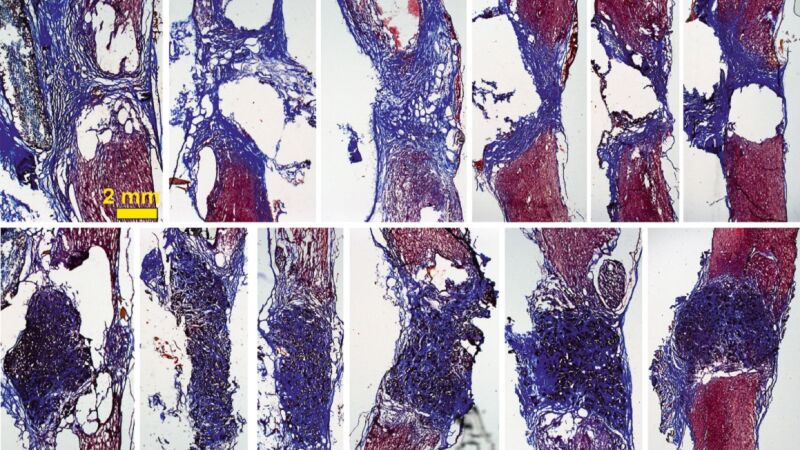

De esta manera, cuando se coloca el scaffold en la médula espinal –en este caso en un modelo de rata con la médula espinal completamente seccionada a nivel torácico–, "vemos que aparecen gran cantidad de vasos sanguíneos, que son fundamentales para nutrir el nuevo tejido, y neuritas (los filamentos que unen unas neuronas con otras)".

La investigadora explica que con esto se observa “cómo las neuronas que han sobrevivido en la zona alrededor de la lesión proyectan sus prolongaciones a través del scaffold y lo invaden en toda su extensión 3D". Todo esto, además, mejora con el tiempo: los resultados son incipientes tras 10 días de implante, pero son mucho más prometedores a los 4 meses.

"Nuestros scaffolds de óxido de grafeno reducido favorecen el crecimiento de vasos sanguíneos más abundantes y más grandes, y neuritas más abundantes, más largas y, además, distribuidas de manera más homogénea en el espacio de la lesión", destaca Serrano.